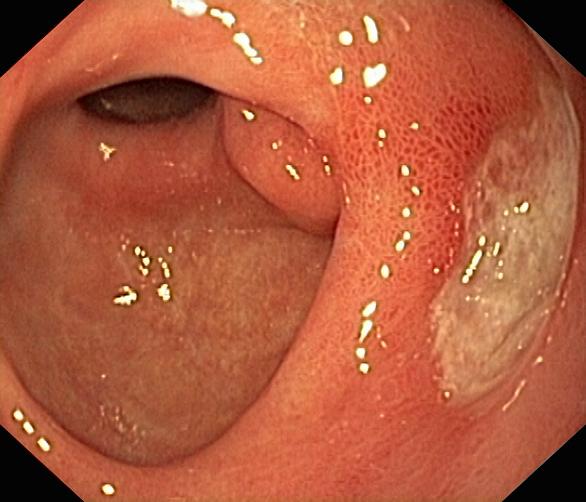

Wrzód trawienny